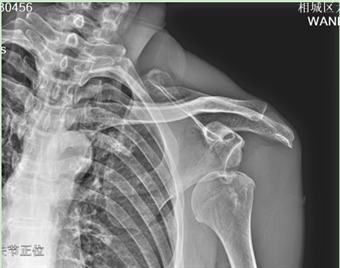

近日,喜欢锻炼的吴大爷去公园锻炼时不慎摔倒,习惯性用左手撑地,只听“咔哒”一声,左肩部疼痛剧烈,活动受限。吴大爷急忙来元和街道社区卫生服务中心中医馆就诊,一拍片发现,虽然没有骨折,但是左肩关节脱位了。

副主任中医师陆金男仔细查看伤情后,立即与主任中医师赵维杰协同对其行肩关节脱位手法复位。凭借丰富的临床经验,两位医生运用椅背复位法成功为吴大爷完成肩关节复位,吴大爷疼痛当即缓解,连声称赞两位医生医术高超,并竖起了大拇指。随后陆医生给吴大爷进行患肢固定,用绷带将左上肢悬吊固定于胸前。